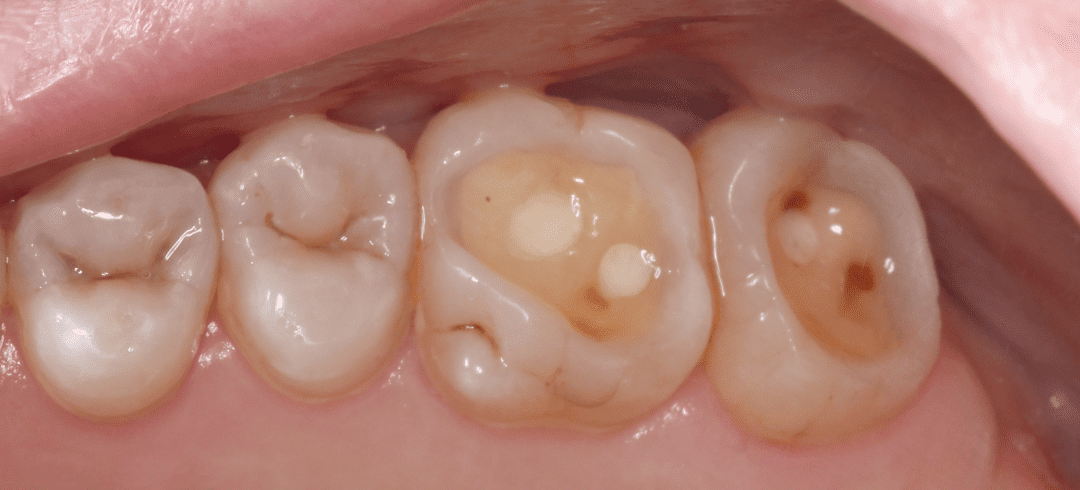

Восстановление эстетики с помощью виниров и вкладок (часть 2)

Восстановление эстетики с помощью виниров и вкладок (часть 1)